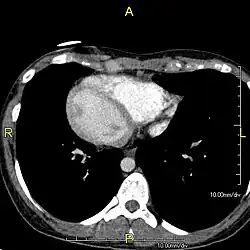

Axial CT image showing dextrocardia and situs inversus in a patient with Kartagener syndrome.